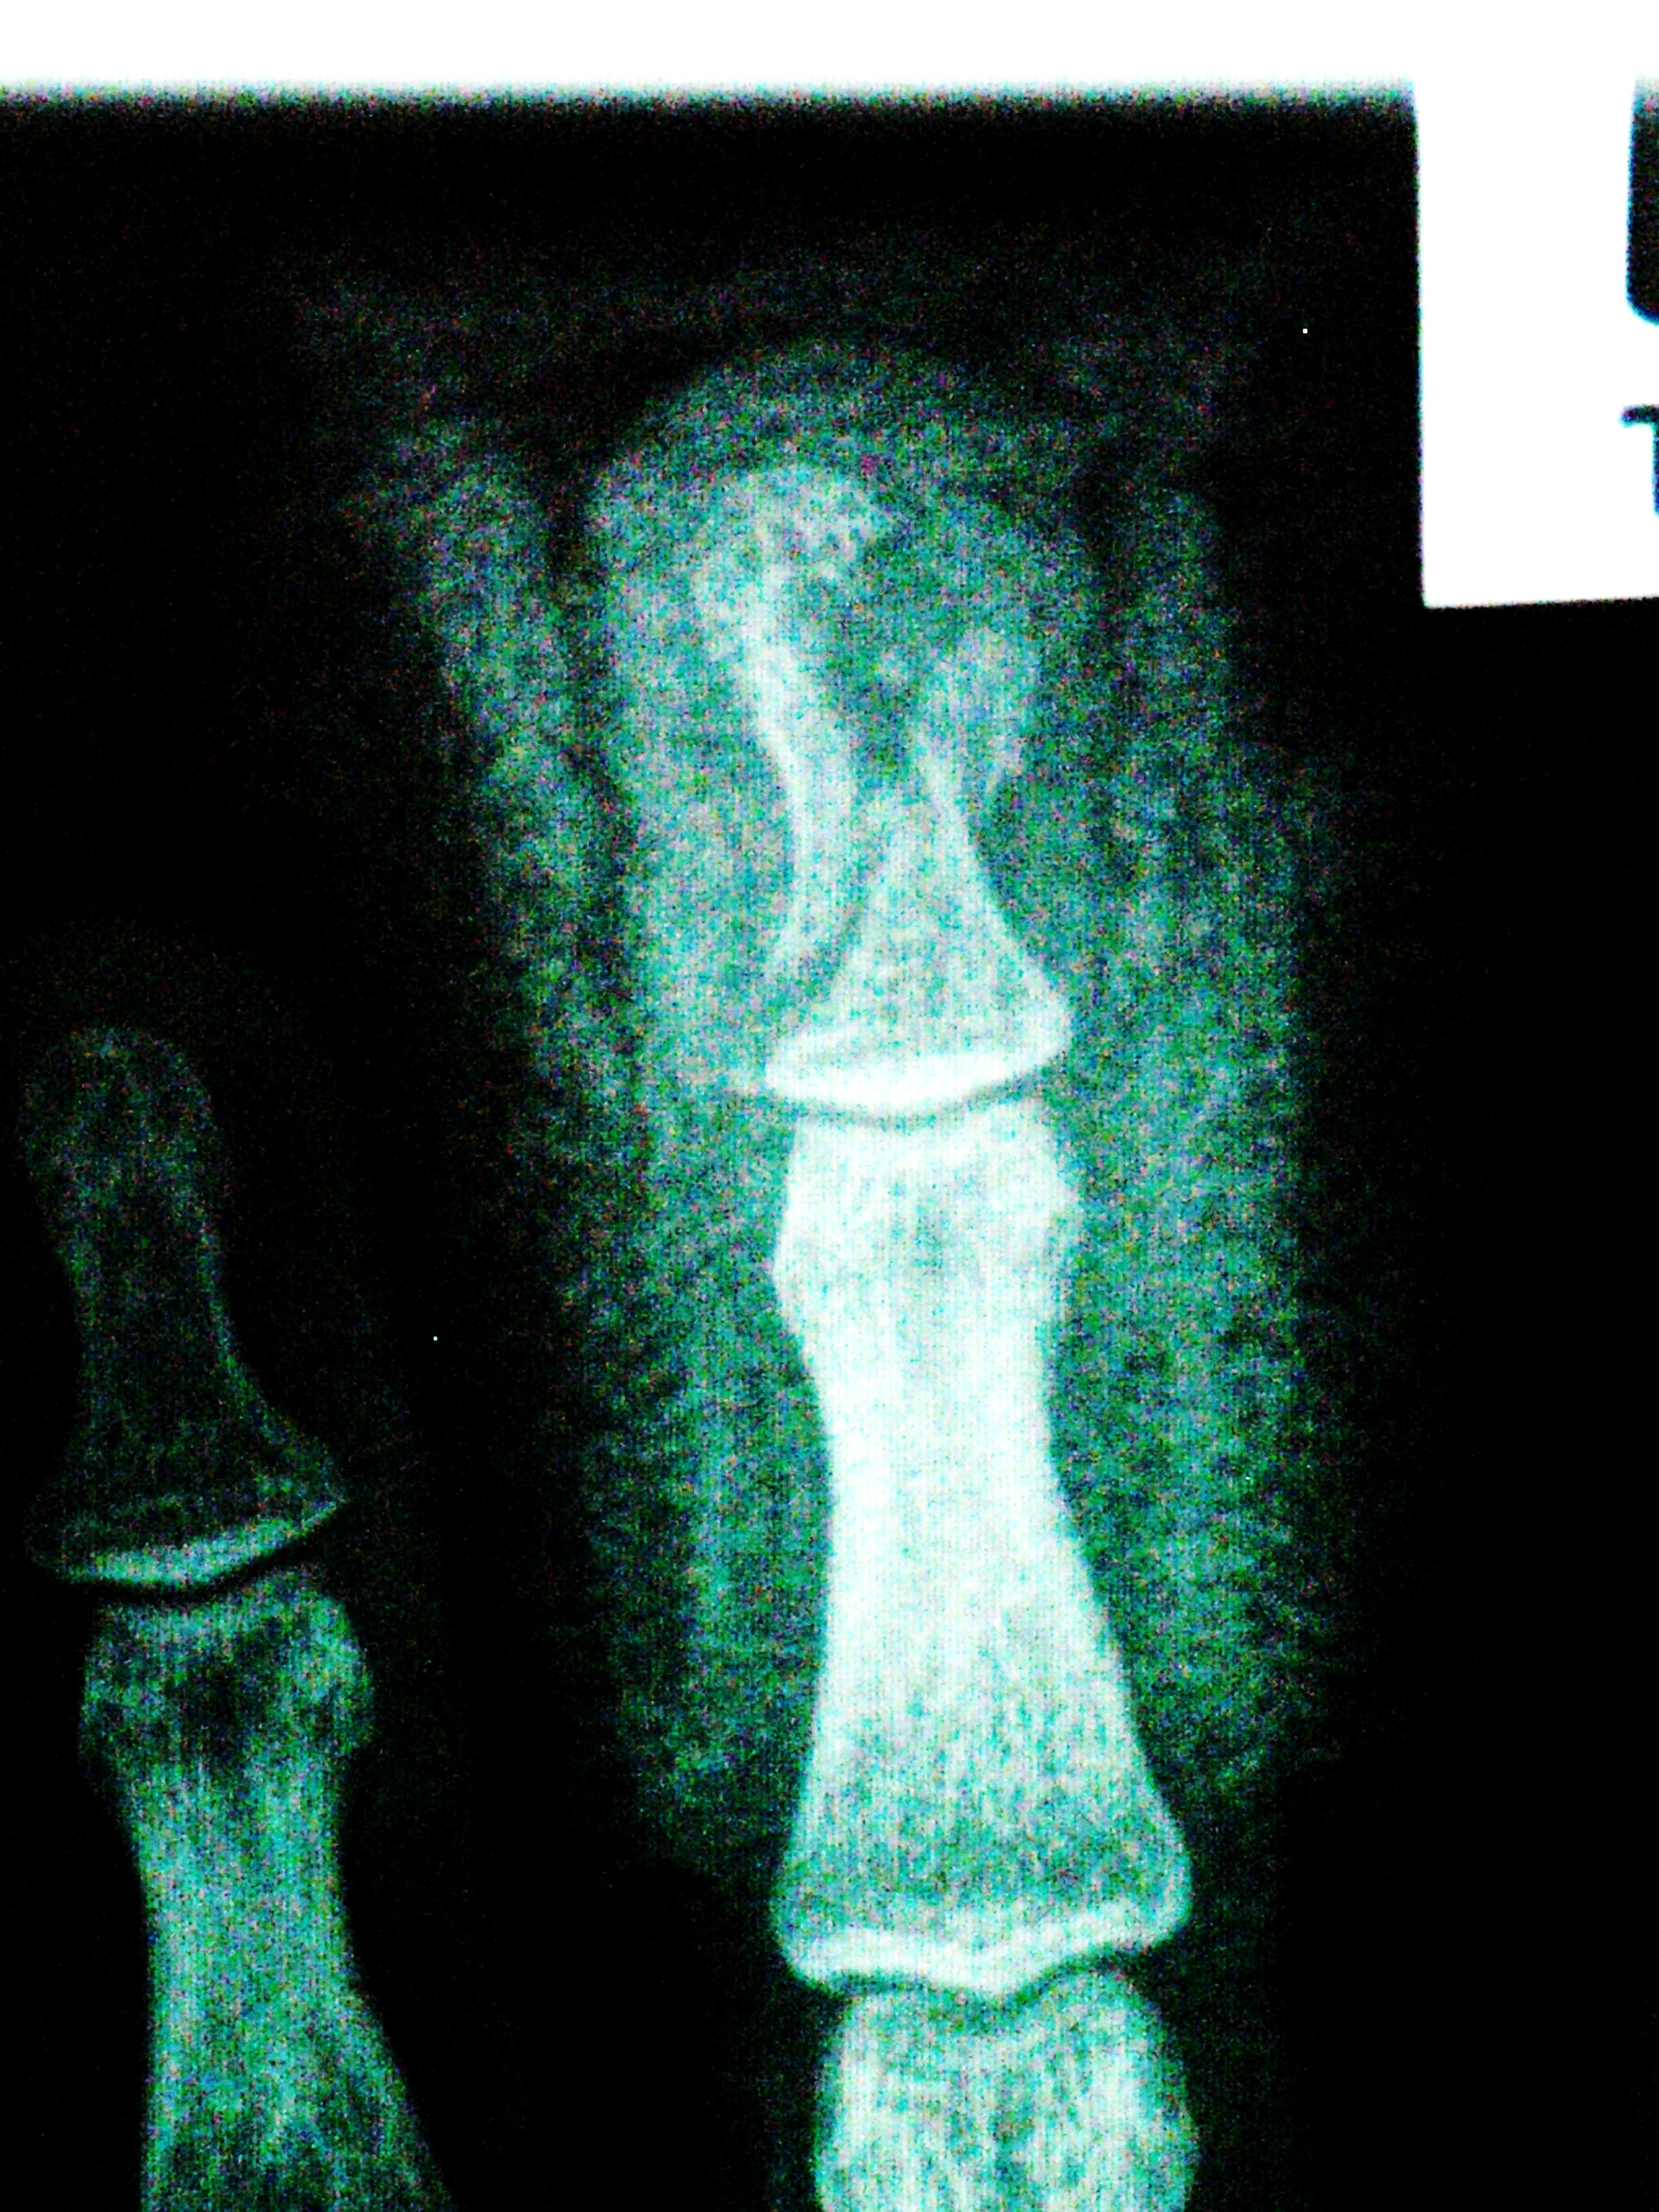

X-ray of break from above. Gap is where hole in my finger was